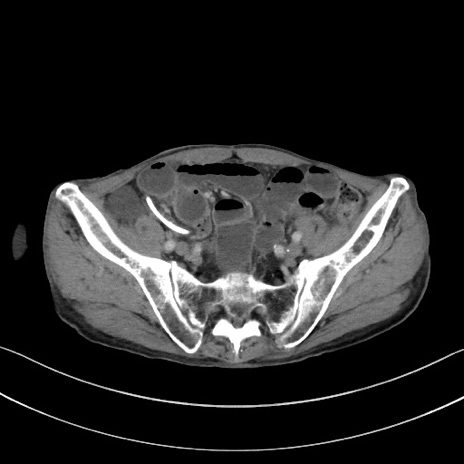

症例3(横断像)

【症例】 70歳代男性

【主訴】右鼠径部腫瘤、疼痛

【現病歴】本日朝より上記主訴あり、受診。

【既往歴】膀胱癌にて膀胱全摘、両側尿管皮膚瘻

【データ】WBC 5600、CRP 0.56